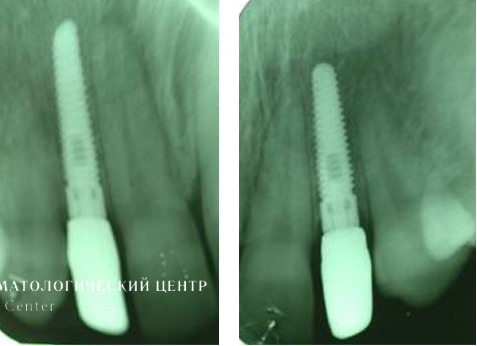

Для устранения эффекта серой, синюшной десны выполнены эстетические безметаллловые оксидциркониевые реставрации. Представленные рентгенограммы демонстрируют успешную имплантацию и максимальную точность прилегания конструкции, а иллюстрации после окончания лечения убеждают в гарантированном достижении желаемого эстетического результата, в частности в наиболее сложной с точки зрения геометрии эстетики десневой зоне.